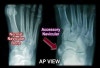

Foot DP, lateral, oblique view를 촬영합니다.

X-ray : 부주상골 증후군(Accessory navicular)